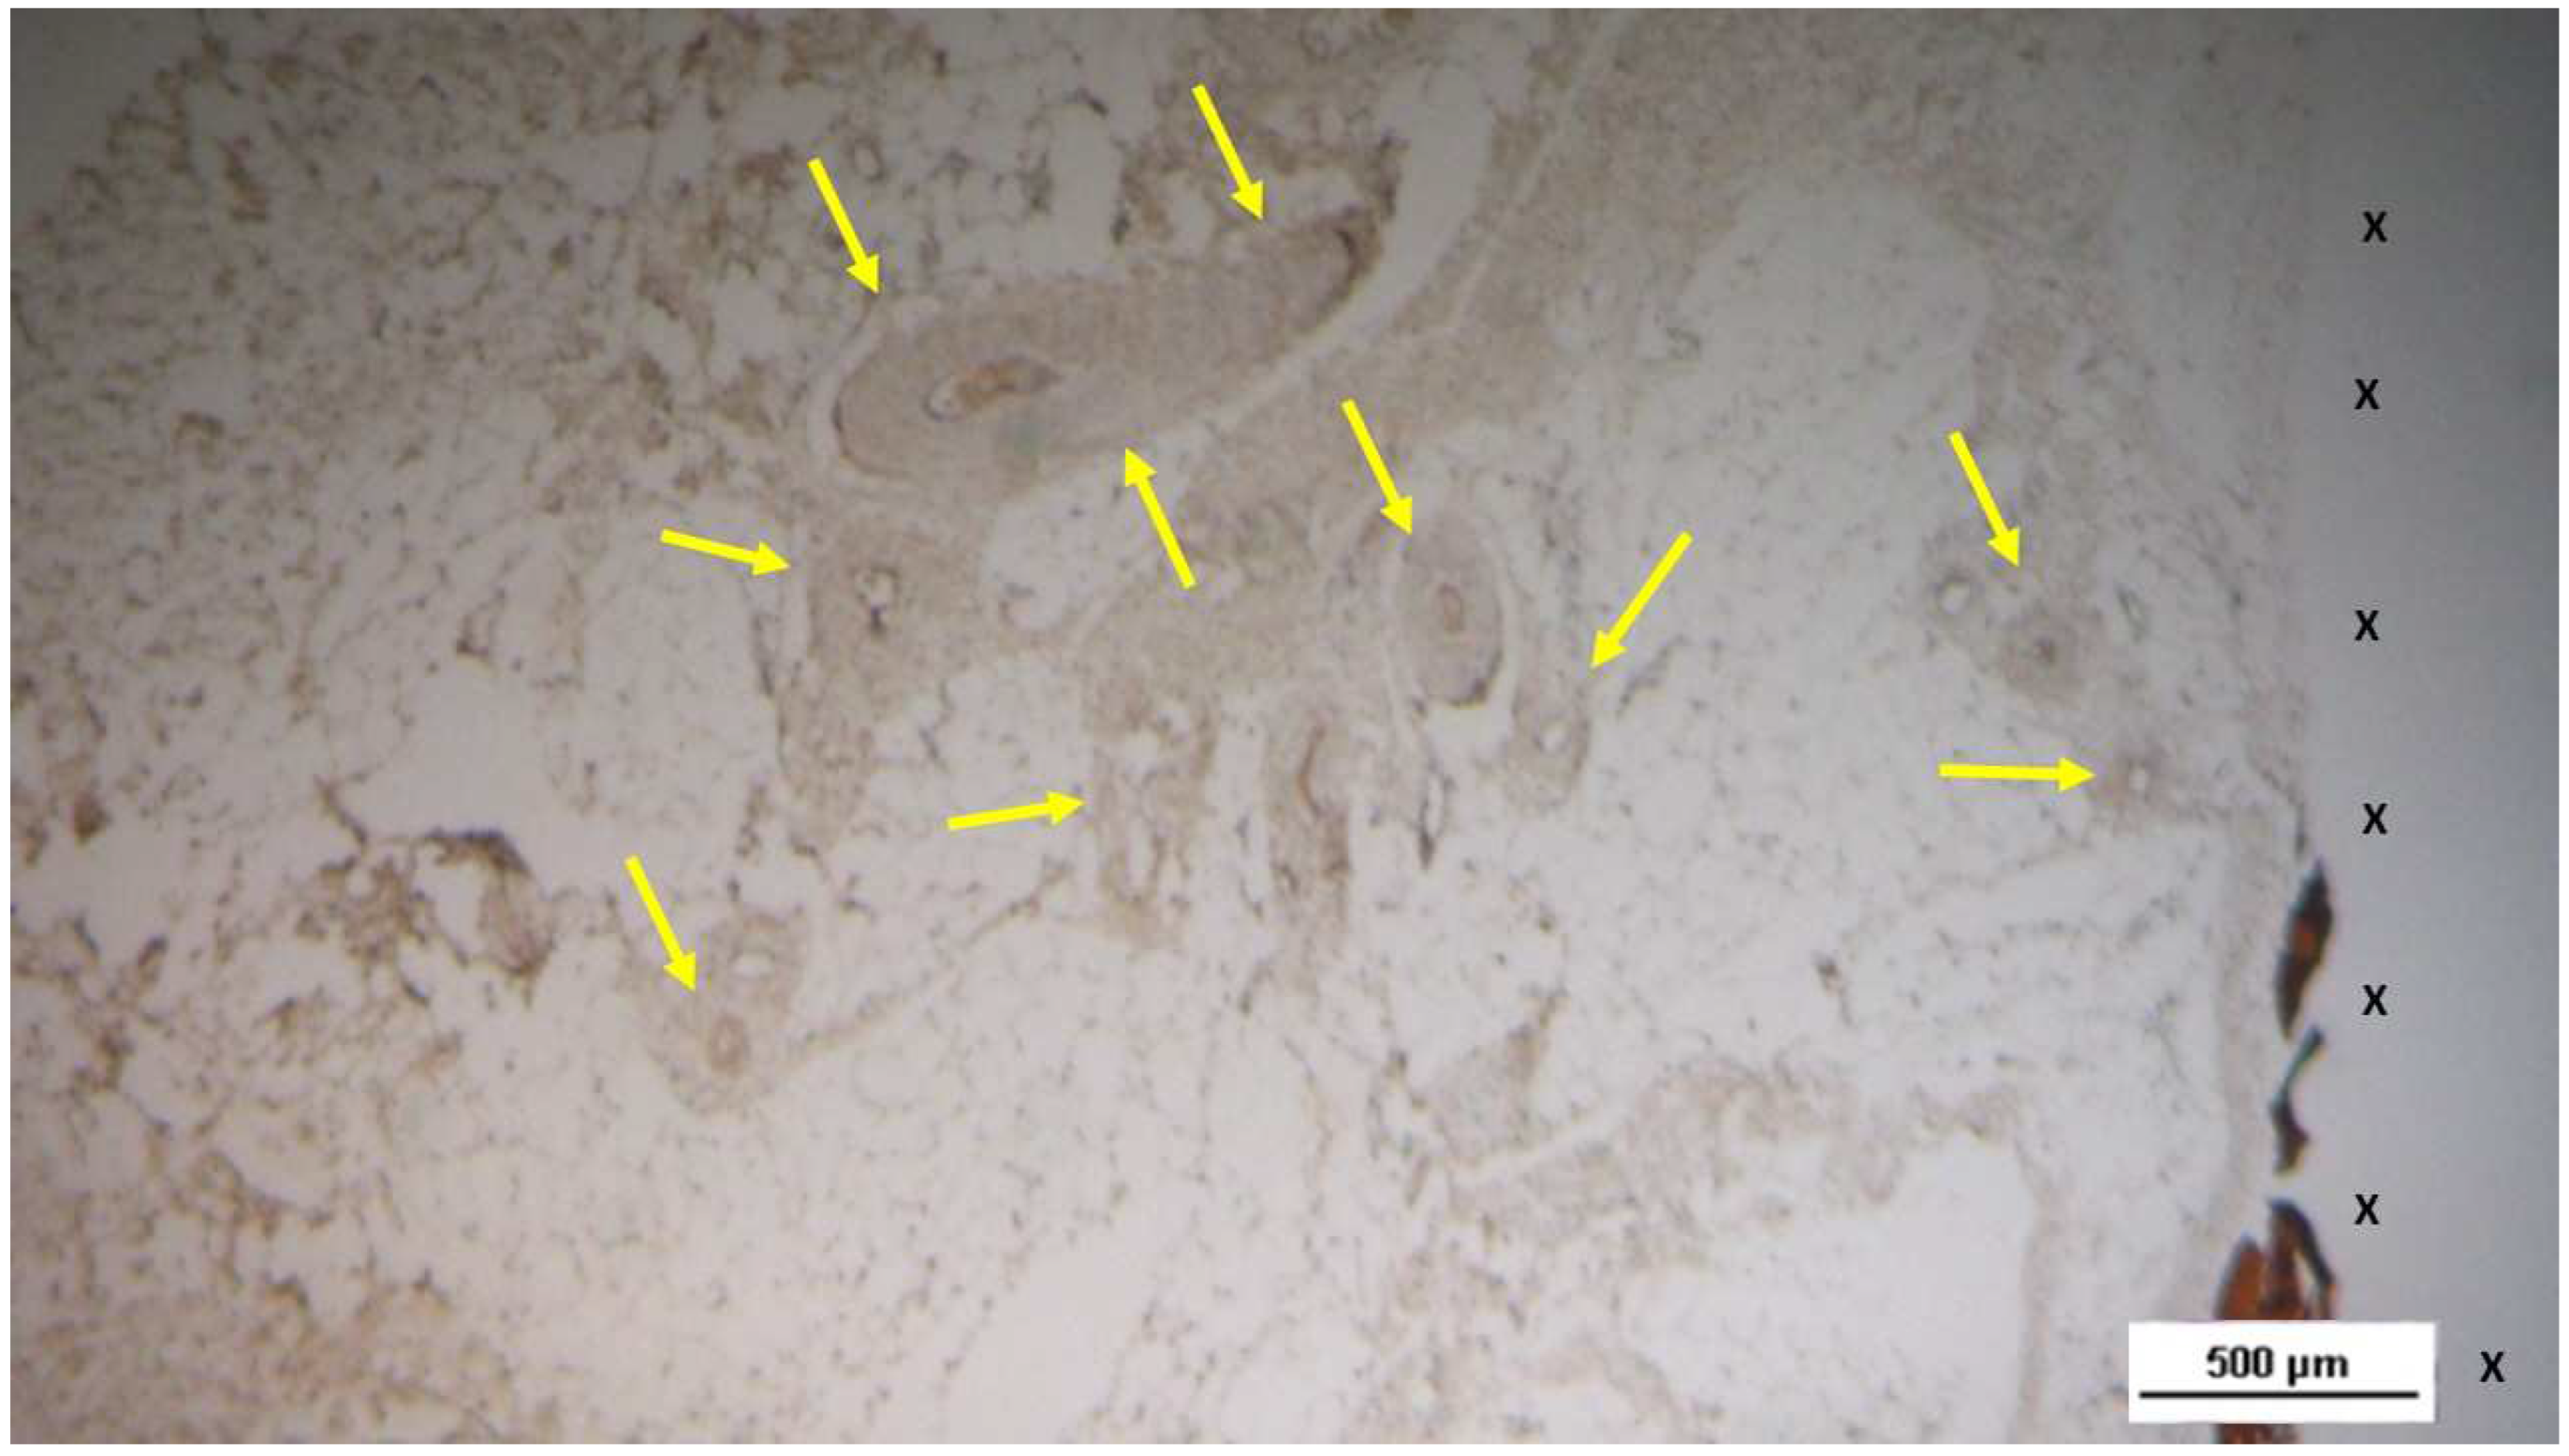

Figure 8. Biopsy sample excised 4 months post-implantation (Midterm –MT). Several arterial elements (yellow arrows) are evident near the TPE fabric of the 3D scaffold (X). Adjacent to the growing muscular layer, VEGF-positive endothelial cells line the lumen of the vessels. VEGF 25X).